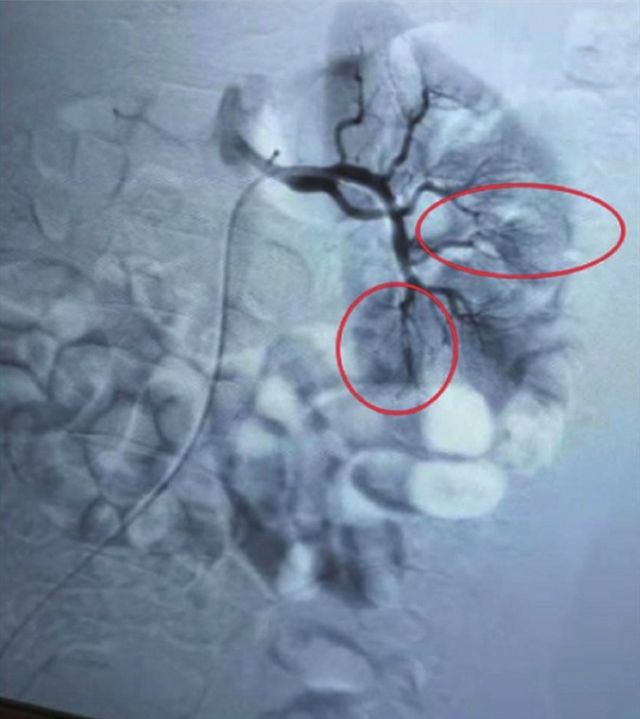

治疗后可见肾动脉及其分支显彰,未见明显充盈缺损、狭窄,肾脏下极未显彰

经过泌尿肾病中心精心治疗和护理,两日后,张克勤教授为刘先生行第二次左肾动脉造影术,以明确他的溶栓情况。造影提示肾动脉及其分支显影可,溶栓有效,梗死面积由70%减少至5%,肾功能完全恢复,刘先生的肾脏保住了!救治很成功,刘先生拔管后第二天就下床进行活动,6天后转回下级医院进行后续治疗。